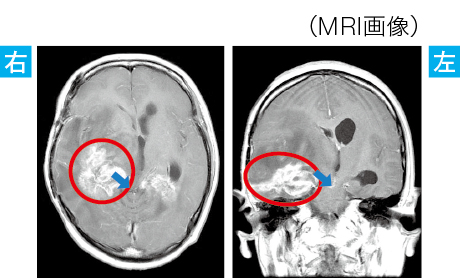

■脳腫瘍による脳ヘルニアの例

●腫瘍が増大することで、慢性頭蓋内圧亢進症状である頭痛・嘔吐が出現した

●腫瘍が中脳を圧迫することで鉤ヘルニア(③)へ移行が進み、右の瞳孔径が散大、意識障害が出現した

●血圧が上昇し、クッシング現象が出現しはじめた